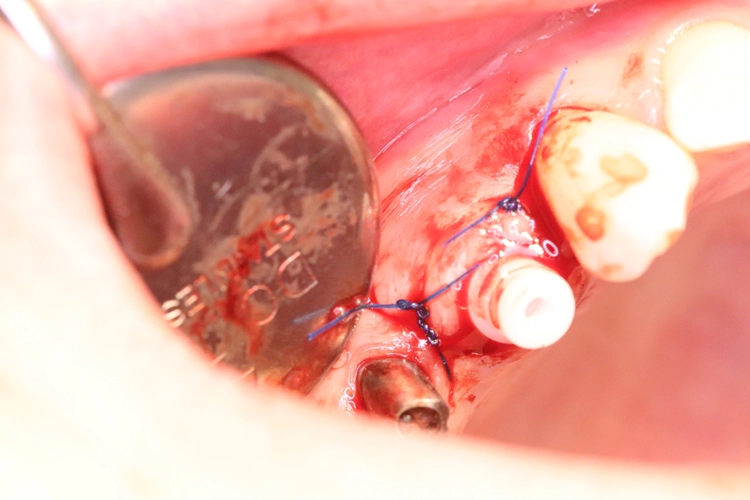

Der Erhalt der Weichgewebsstrukturen und des Kieferkamms wurde durch das Einbringen eines Knochenaufbaumaterials im Sinne einer Socket/Ridge Preservation ohne Membran gewährleistet (Abb. 5). Mesial zum 13 wurde eine resorbierbare Naht (SABAsorb rapid) gesetzt, um die Weichgewebe zu adaptieren. Die Kontrolle des Heilungsverlaufs nach dem Eingriff erfolgte ein Tag später (Abb. 6).

Während der Phase des Wundverschlusses ging ein geringer Bruchteil (1-2 %) des Knochenersatzmaterials verloren. Daher wird empfohlen, immer bis zum Gingivaniveau zu augmentieren. Dieser leichte Verlust spielt keine Rolle für den weiteren Knochenaufbau, der Patient merkt lediglich ein paar „Krümel“ im Mundraum.